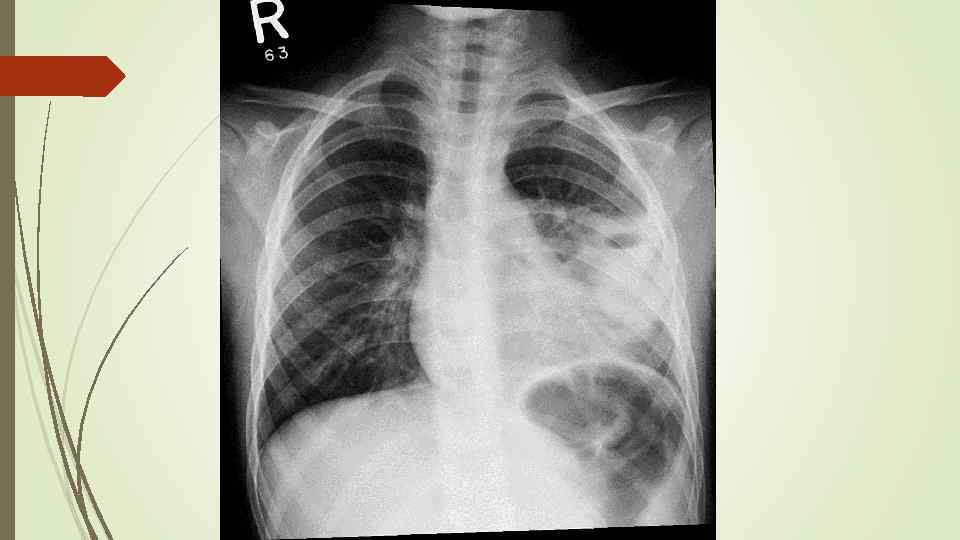

Через неделю

Через неделю

Через 5 недель

Через 5 недель